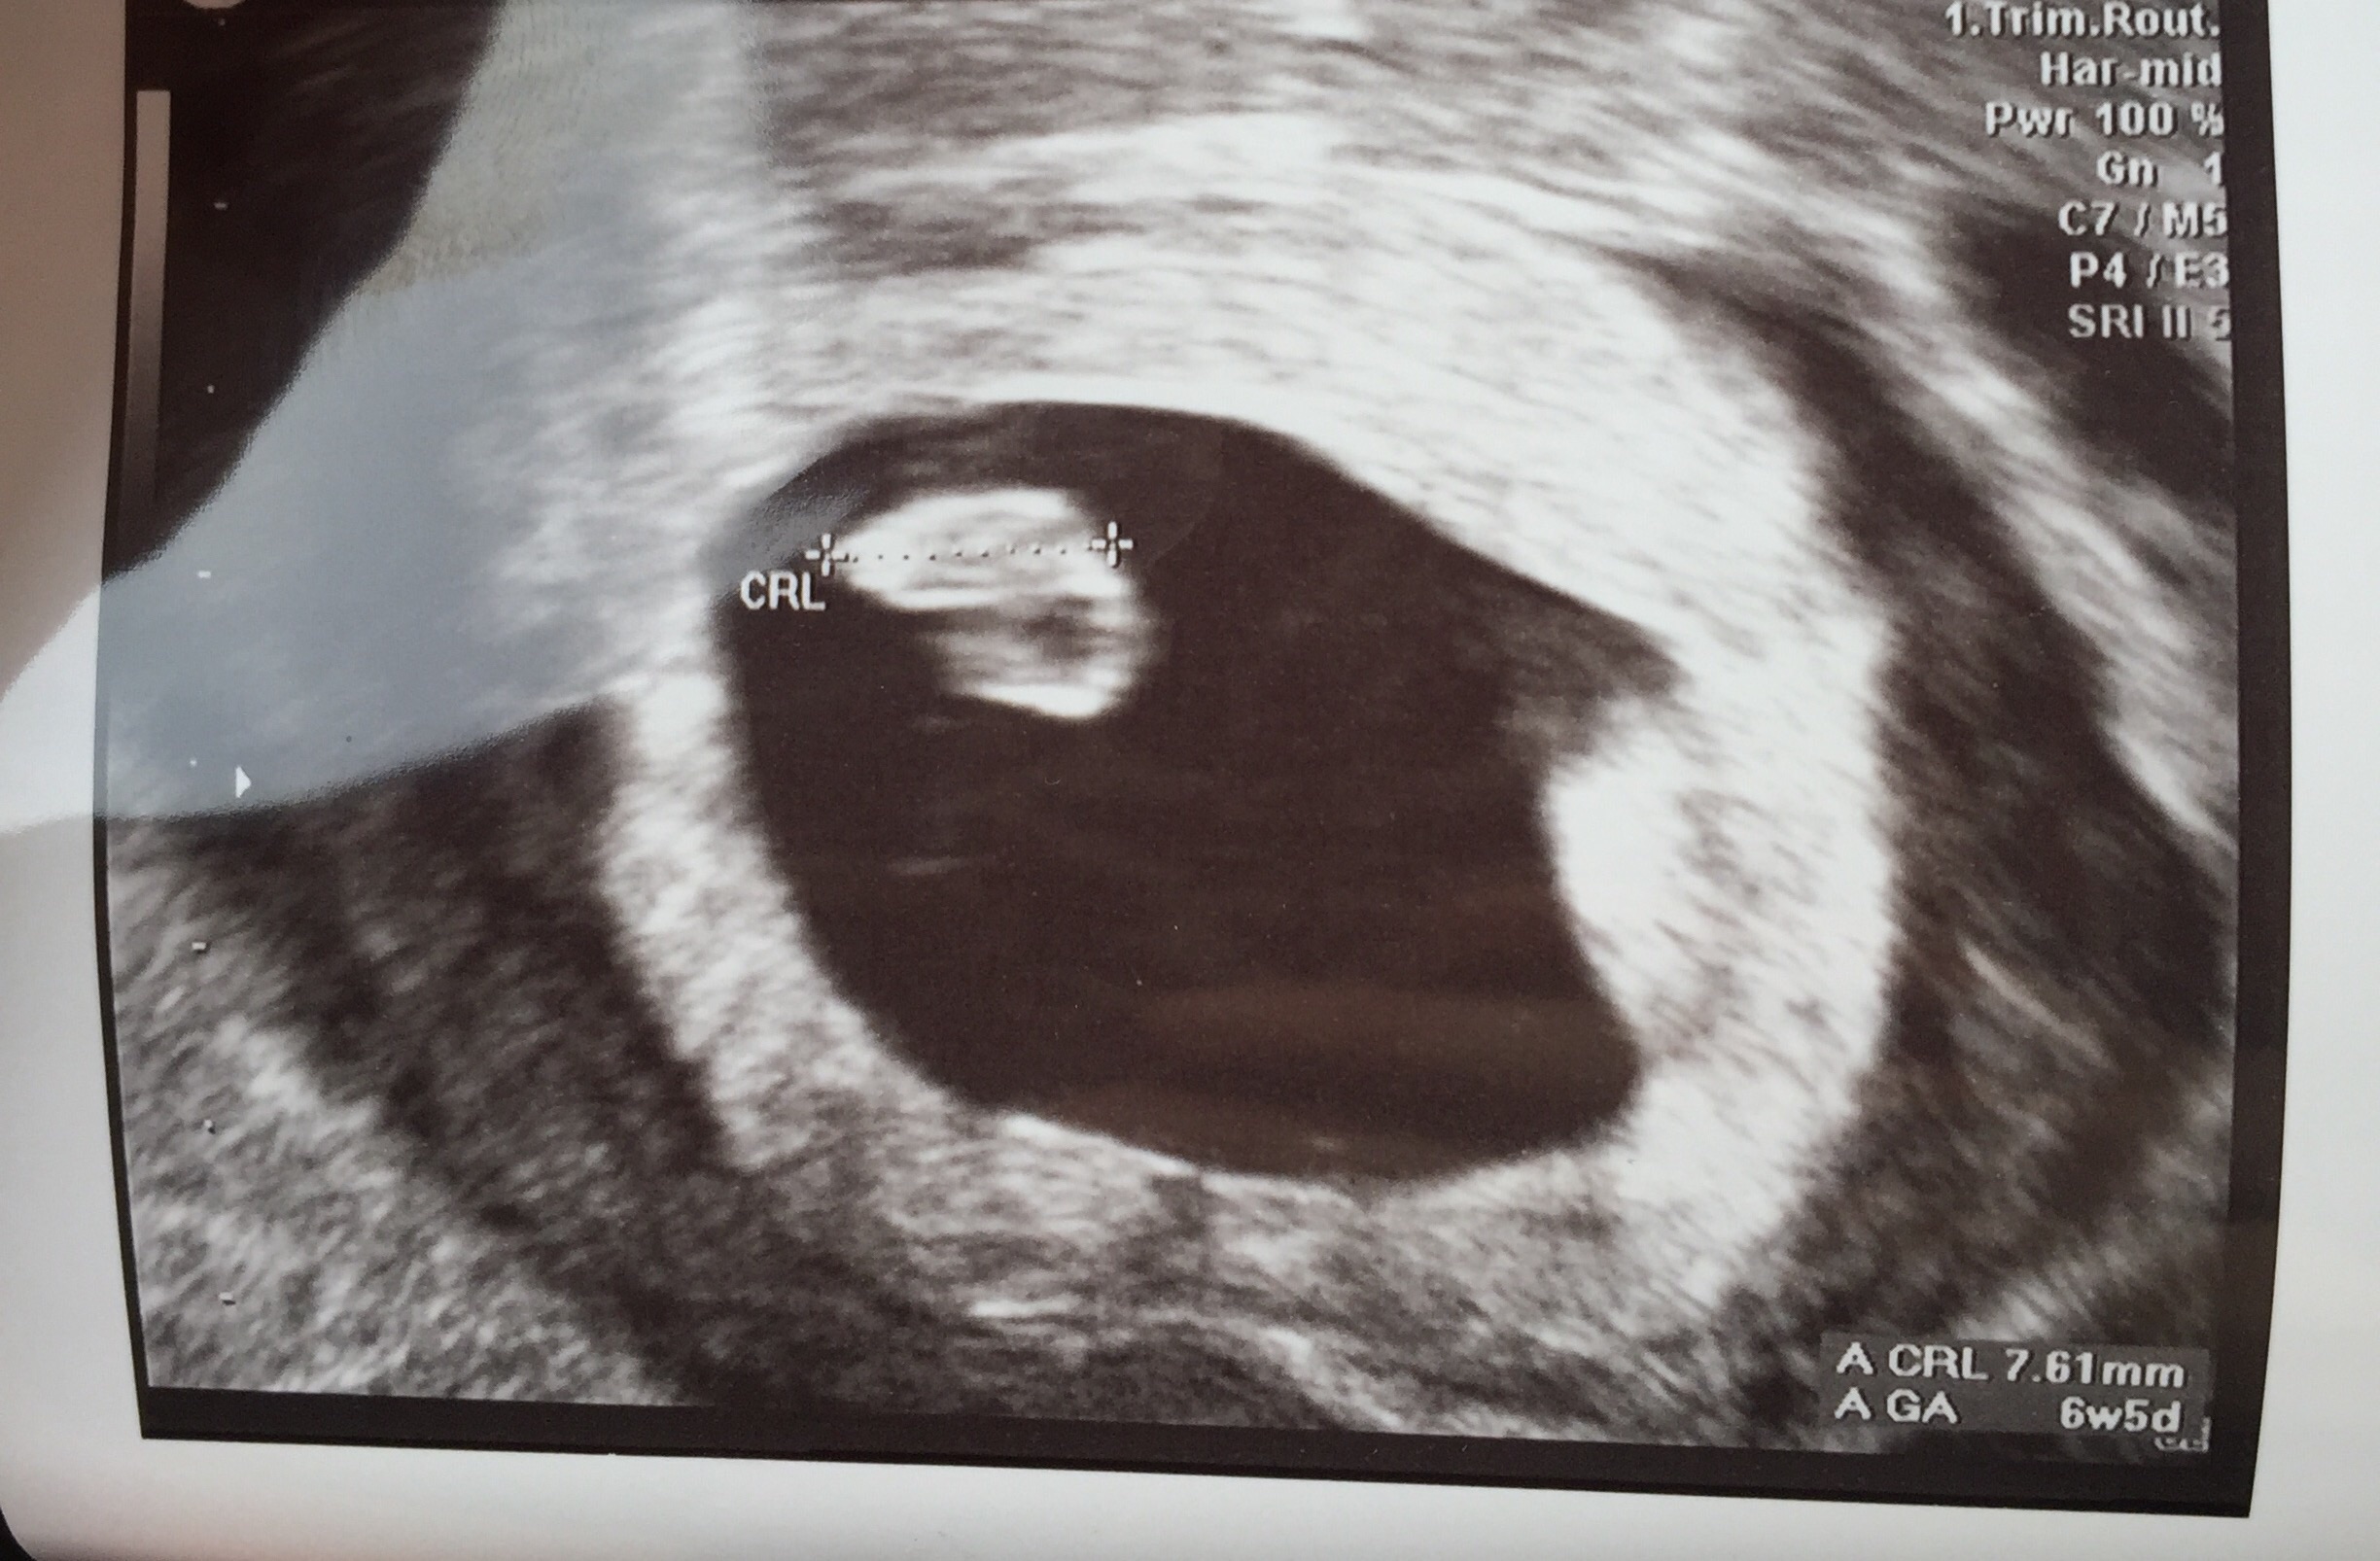

• 6 weeks 4 days